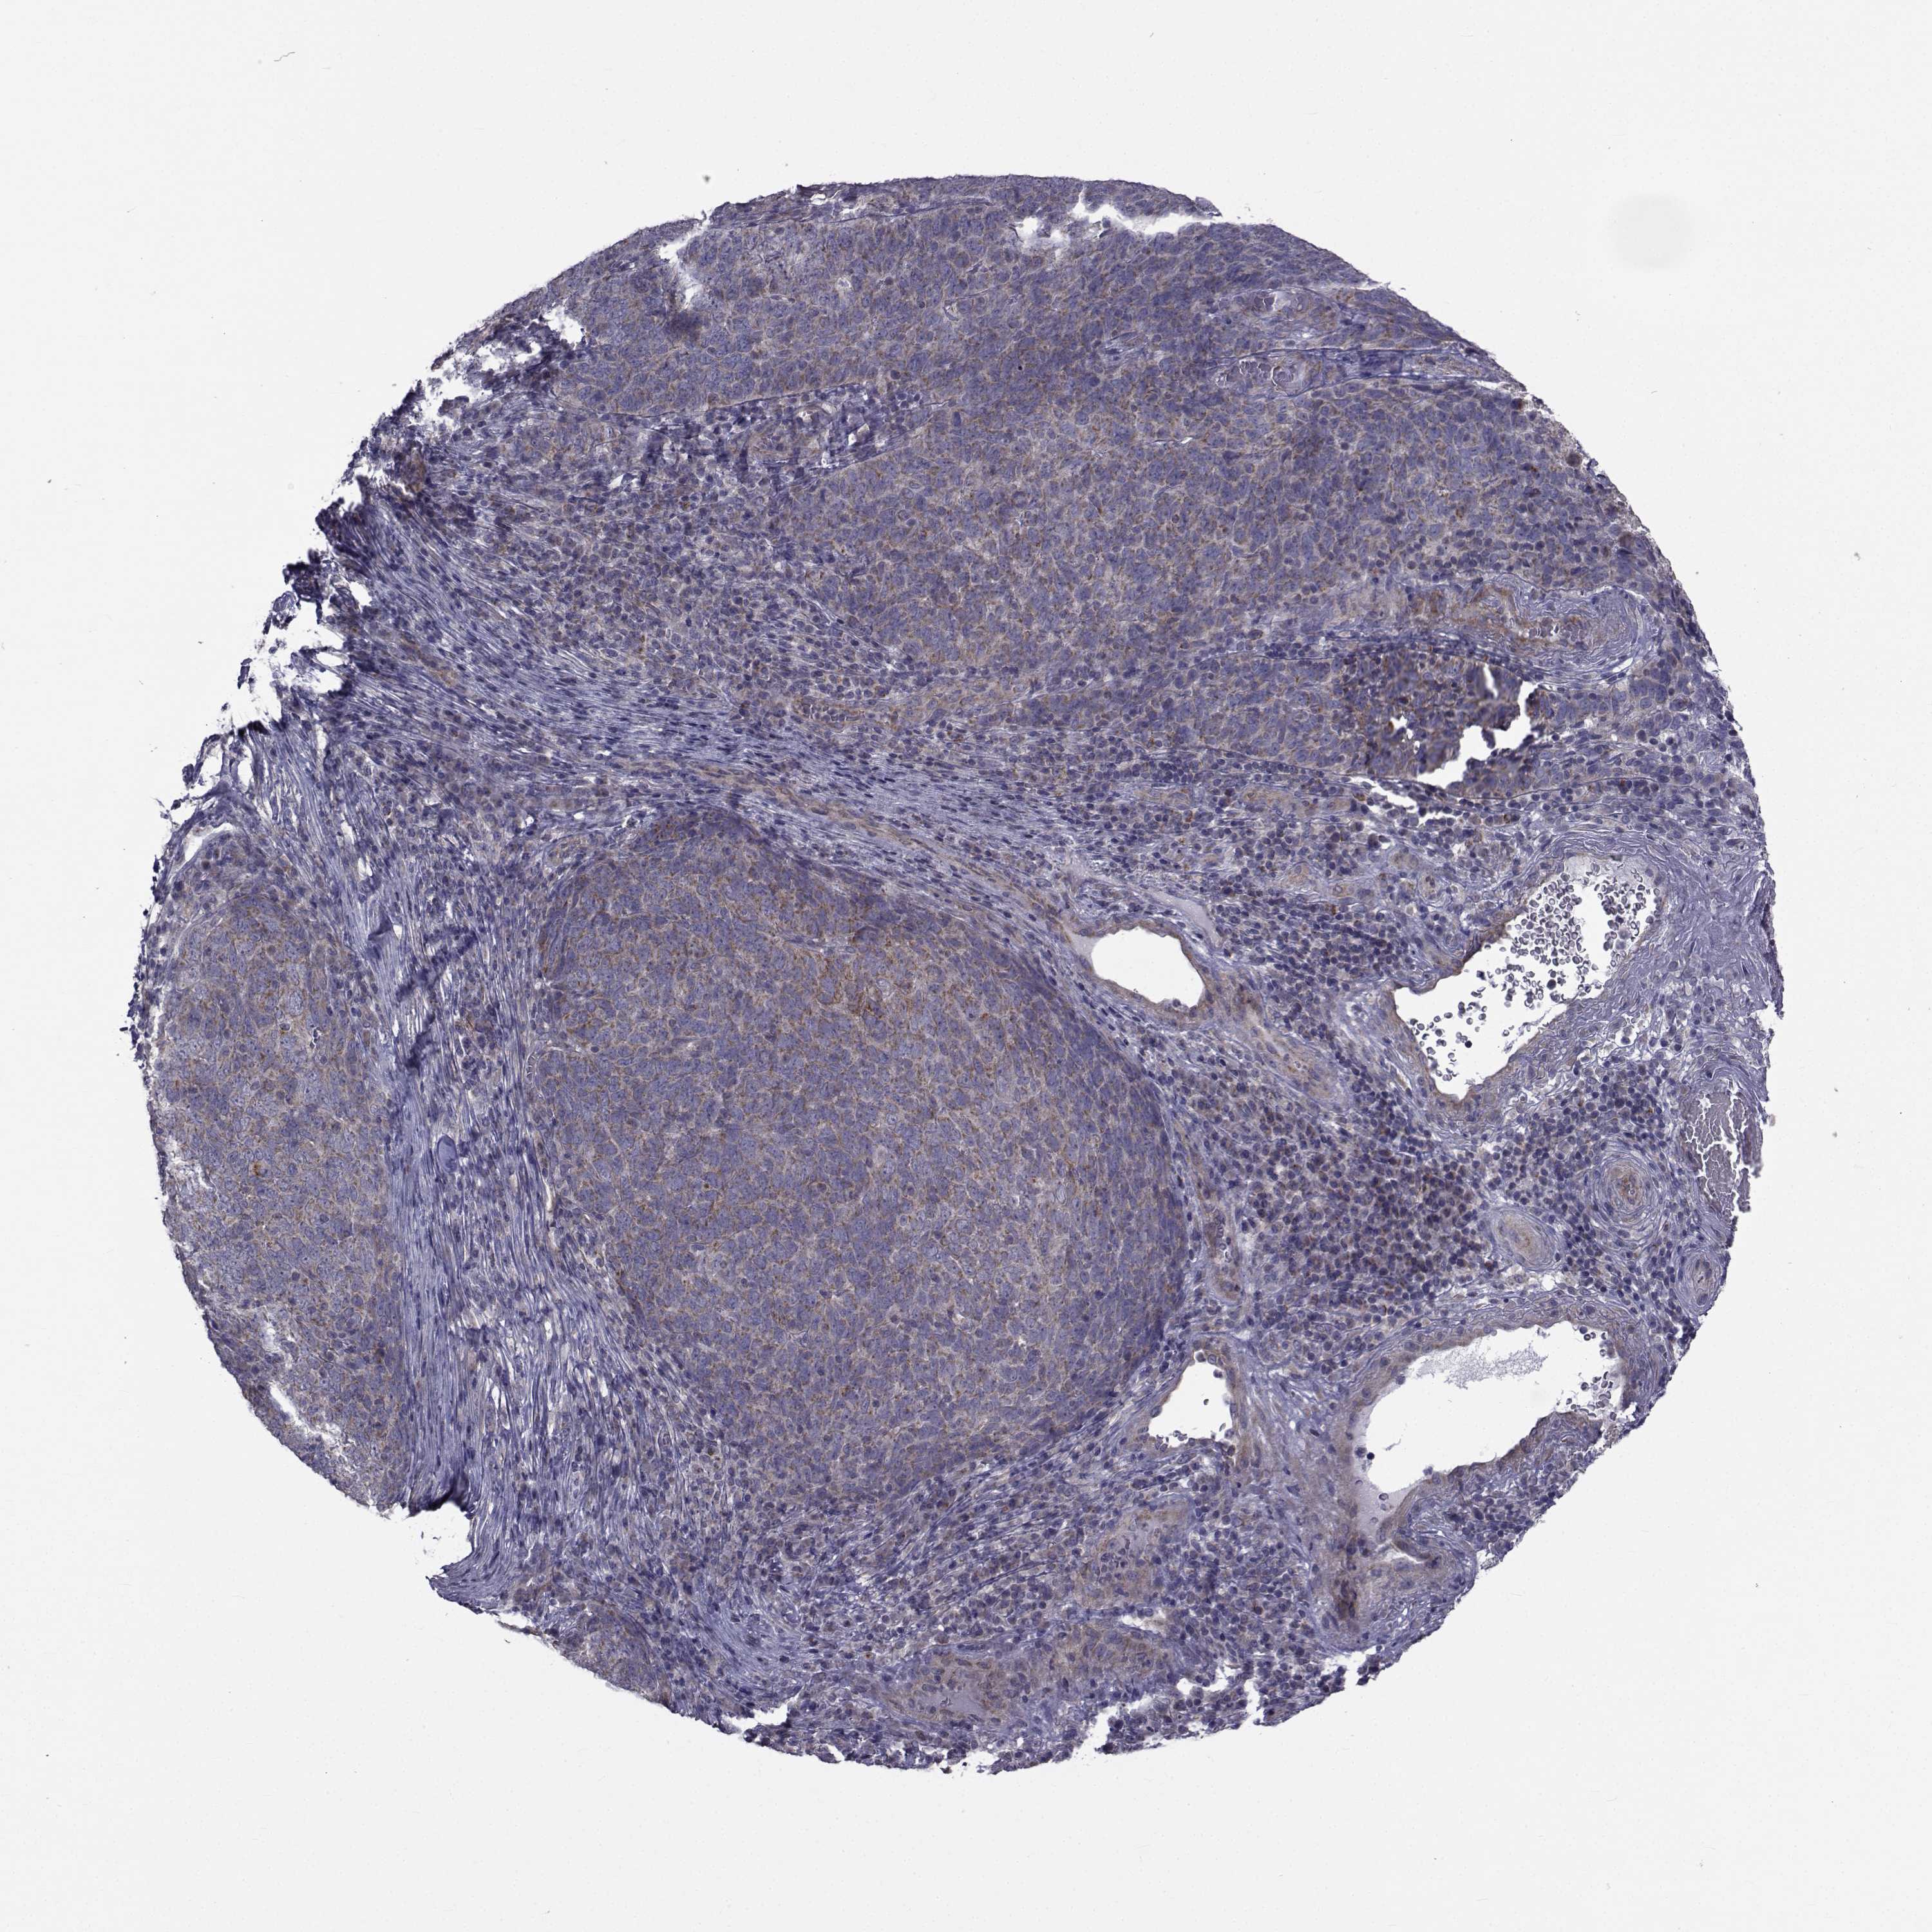

SKIN CANCER - Protein expressioni

A mouse-over function shows sample information and annotation data. Click on an image to view it in a full screen mode. Samples can be filtered based on level of antibody staining by selecting one or several of the following categories: high, medium, low and not detected. The assay and annotation is described here.

Each image is clickable and will lead to virtual microscopy that enables deeper exploration of all samples and also displays staining intensity scores, fraction scores and subcellular localization as well as patient and tissue information for each sample.

Antibody HPA028521

Antibody HPA029274

Antibody HPA030240

Staining

High

Medium

Low

Not detected

Intensity

Strong

Moderate

Weak

Negative

Quantity

>75%

75%-25%

<25%

None

Location

Nuclear

Cytoplasmic/membranous

Cytoplasmic/membranous,nuclear

Basal cell carcinoma

Squamous cell carcinoma, NOS